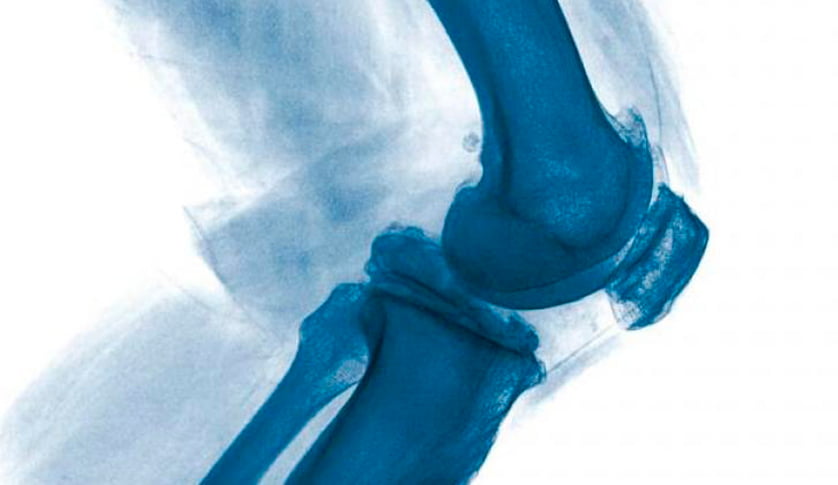

Артроскопія колінного суглобу: пластика передньої хрестоподібної зв’язки